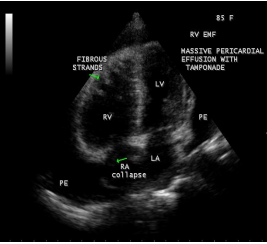

Case 3. (Right ventricular endomyocardial fibrosis with massive pericardial effusion in a 85 –year old male)

A 85-year old obese female was admitted in the cardiac intensive care unit with breathlessness. X-ray chest revealed massive pericardial effusion with calcification in the right ventricular region as shown in Figure 16. ECG revealed low voltage complexes. Blood chemistry revealed normal. Transthoracic echocardiography revealed large pericardial effusion with Right ventricular apical fibrosis, suggesting right ventricular endomyocardial fibrosis as shown in Figure 17 with tamponade physiology as in Figure 18 and treated with pericardiocentesis and pericardial fluid revealed an exudate on biochemical analysis.

Figure 17: Apical four chamber view suggesting RV apical fibrosis with massive pericardial effusion

Figure 29: 2D Echocardiographic imaging showing massive pericardial effusion with ‘cobra-head’

fibrous strands in the pericardial sac suggesting the burnt- out stage of endomyocardial fibrosis in a 60-year old male.

A large pericardial effusion is often present and noted as another peculiar feature of this disease [27]. Pericardial effusion and ascites dominate the clinical picture of right ventricular EMF [28], [29], [30]. Etiology of pericardial effusion is possibly inflammatory and EMF is to be considered as ‘pancarditis’ since all the layers are involved. Adhesions between the parietal and visceral layers of the pericardial sac may develop and visible as strong fibrotic strands as shown in Figures 29. A right ventricular EMF presented with massive pericardial effusion was detected in a 85 –year old female as shown in Figure 16, 17 and 29[31]. Cardiomegaly can be exaggerated by pericardial effusion, and pleural effusion is also a common finding as shown in Figure 9 [16-Figure 2]. Giant ascites in EMF is not fully explained by congestion alone and it is due to peritoneal inflammation and reduced reabsorption of peritoneal fluid, caused by fibrosis since the fluid is an exudate with predominant lymphocytes. The triad of elevated JVP (Jugular venous pressure), ascites and hepatomegaly formed the hallmark of right ventricular EMF.